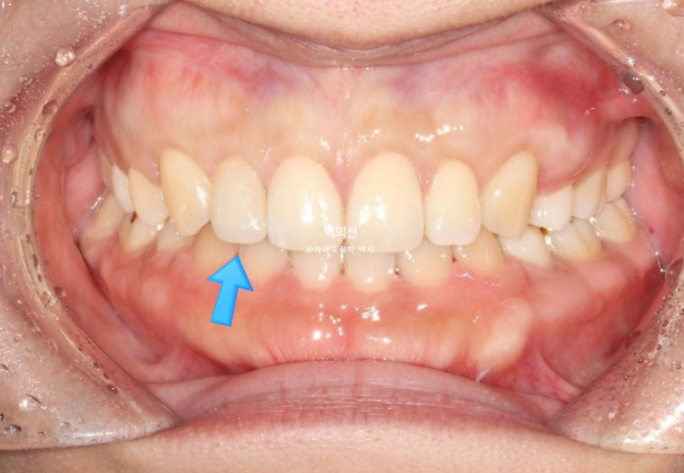

정답은 파란 화살표 치아가 바로 젤라미입니다.

25.07

왜소치는 무삭제 라미네이트 젤라미로 깔끔하게 수복되었습니다.